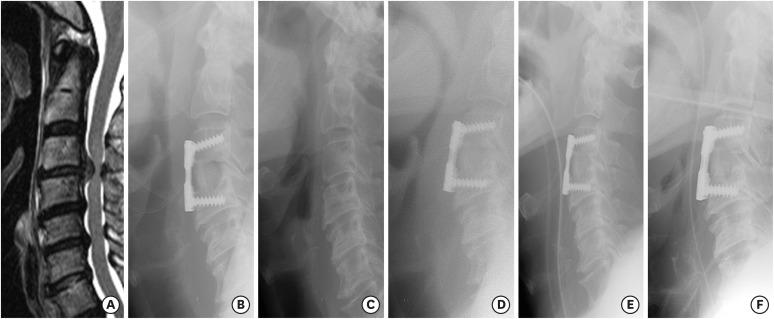

分析与颈椎前路手术后长时间插管或再次插管相关的危险因素。

Analysis of the Risk Factors Associated with Prolonged Intubation or Reintubation after Anterior Cervical Spine Surgery.

Standardized postoperative airway management is essential for patients undergoing anterior cervical spine surgery (ACSS). The paucity of clinical series evaluating these airway complications after ACSS has been resulted in a significant limitation in statistical analyses.

METHODS

A retrospective cohort study was performed regarding airway distress (intubation for more than 24 hours or unplanned reintubation within 7 days of operation) developed after ACSS. If prevertebral soft tissue swelling was evident after the operation, patients were managed with prolonged intubation (longer than 24 hours). Preoperative and intraoperative patient data, and postoperative outcome (time to extubation and reintubation) were analyzed.

RESULTS

Between 2008 and 2016, a total of 400 ACSS were performed. Of them, 389 patients (97.25%) extubated within 24 hours of surgery without airway complication, but 11 patients (2.75%) showed postoperative airway compromise; 7 patients (1.75%) needed prolonged intubation, while 4 patients (1.00%) required unplanned reintubation. The mean time for extubation were 2.75 hours (range: 0-23 hours) and 50.55 hours (range: 0-250 hours), respectively. Age ( = 0.015), diabetes mellitus ( = 0.003), operative time longer than 5 hours ( = 0.048), and estimated blood loss (EBL) greater than 300 mL ( = 0.042) were associated with prolonged intubation or reintubation. In prolonged intubation group, all patients showed no airway distress after extubation.

CONCLUSION

In ACSS, postoperative airway compromise is related to both patients and operative factors. We recommend a prolonged intubation for patients who are exposed to these risk factors to perform a safe and effective extubation.